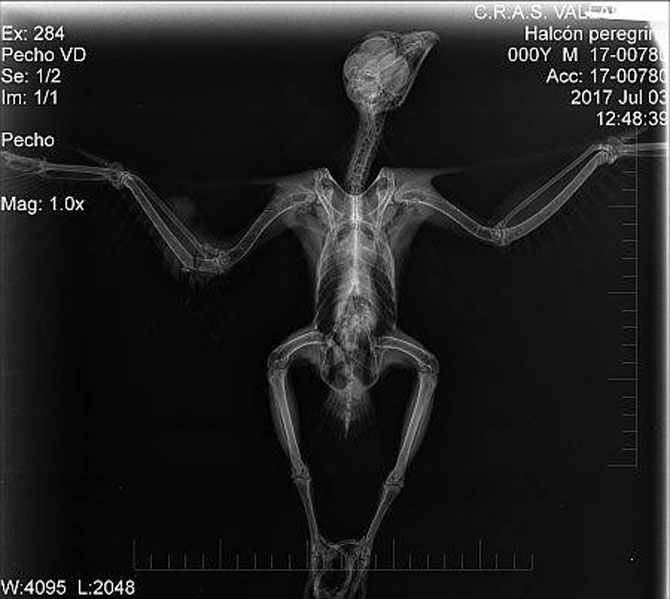

El ave llegó al centro hace algo más de un mes con una fractura doble de cubito y radio en su ala derecha, y se encontraba muy delgado con sólo 363 gramos de peso, según la Fundación del Patrimonio Natural, de la que depende el centro.

Los veterinarios y demás profesionales del centro pensaron que la causa era la inexperiencia del animal, y que los traumatismos habían sido causados en sus primeros vuelos exploratorios.

Los primeros cuidados que ha recibido han consistido en su alimentación, para que ganase peso antes de la intervención quirúrgica, de la que salió satisfactoriamente y de la que ahora se recupera.